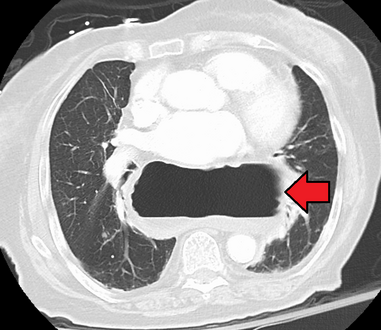

وفي الوقت نفسه، يمكن لقياس الضغط تحديد سلامة حركات المريء ووجود ارتخاء المريء. وتسمح اختبارات الأس الهيدروجيني بالتحليل الكمي لنوبات الارتجاع الحمضي. كما أن التصوير المقطعي المحوسب مفيد في تشخيص مضاعفات الفتق الحجابي مثل الالتواء المعدي، واسترواح الصفاق، واسترواح المنصف.[8]

الفتق الحجابي كما تبينه الأشعة الفوق صوتية.[9]